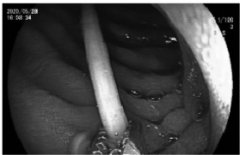

男子喝啤酒时不慎将一根牙签吞下去,医护人员经1小时的“微创”努力,终于顺利将这根7厘米长且两头尖端的牙签取出。医院供图 喝啤酒...